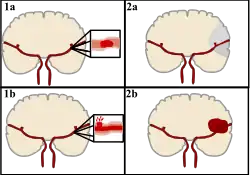

Classification

Stroke can be classified into two major categories: ischemic and hemorrhagic.[20] Ischemic stroke is caused by interruption of the blood supply to the brain, while hemorrhagic stroke results from the rupture of a blood vessel or an abnormal vascular structure.

About 87% of stroke is ischemic, with the rest being hemorrhagic. Bleeding can develop inside areas of ischemia, a condition known as "hemorrhagic transformation." It is unknown how many cases of hemorrhagic stroke actually start as ischemic stroke.[2]

Ischemic

During ischemic stroke, blood supply to part of the brain is decreased, leading to dysfunction of the brain tissue in that area. There are four reasons why this might happen:

Hemorrhagic

There are two main types of hemorrhagic stroke:[30][31]

- Intracerebral hemorrhage, which is bleeding within the brain itself (when an artery in the brain bursts, flooding the surrounding tissue with blood), due to either intraparenchymal hemorrhage (bleeding within the brain tissue) or intraventricular hemorrhage (bleeding within the brain's ventricular system).

- Subarachnoid hemorrhage, which is bleeding that occurs outside of the brain tissue but still within the skull, and precisely between the arachnoid mater and pia mater (the delicate innermost layer of the three layers of the meninges that surround the brain).